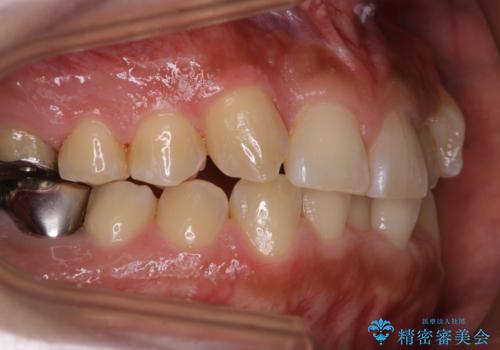

前歯メインにステインの付着が見られ、コース内容を相談した結果PMTC(保険外治療)の30分コースを行いました。

- 矯正治療を考えているため、まずはクリーニングを行いたいとのことで来院されました。PMTC30分コースを行いました。